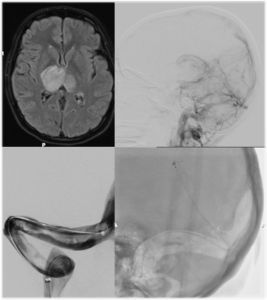

Brain Arteriovenous Malformation (AVM) Embolization

An Arteriovenous malformation or AVM is an abnormal connection between arteries and veins, bypassing the capillary system. This vascular anomaly is widely known because of its occurrence in the central nervous system, but can appear in any location. Although many AVMs are asymptomatic, AVMs in the brain can cause intense headache, intracranial bleeding, and/or lead to other serious medical problems, such as seizures. Vascular malformations can be treated endovascularly with embolization using liquid embolics, such as Onyx and n-BCA, by open surgery, or by gamma knife radiosurgery. Sometimes these lesions are treated by a combination of the above mentioned therapies.

Dural Arteriovenous Fistula (AVF) Embolization

A duralarteriovenous fistula (DAVF) is an abnormal direct connection (fistula) between a meningealartery and a meningeal vein or dural venous sinus. Like other vascular malformations, a dural AVF can be treated endovascularlywith embolization using liquid embolics, such as Onyx and n-BCA, by open surgery, or by gamma knife radiosurgery. Sometimes these lesions are treated by a combination of the above mentioned therapies.

Spinal AVF Embolization

Most spinal fistulas are created when a radiculomeningeal artery feeds directly into a radicular vein near the spinal nerve root. Spinal dural AVFs are most commonly found in the thoracolumbar region. Patients become symptomatic because the AVF creates spinal cord venous congestion and hypertension, resulting in hypoperfusion, hypoxia, and edema of the spinal cord. Due to the slow-flow nature of most spinal dural AVFs, hemorrhage rarely occurs. Most dural AVFs are believed to occur spontaneously, but the exact etiology is still unknown. Again, these types of vascular lesions can be treated endovascularly with embolization using liquid embolics, such as Onyx and n-BCA, and with open surgery.